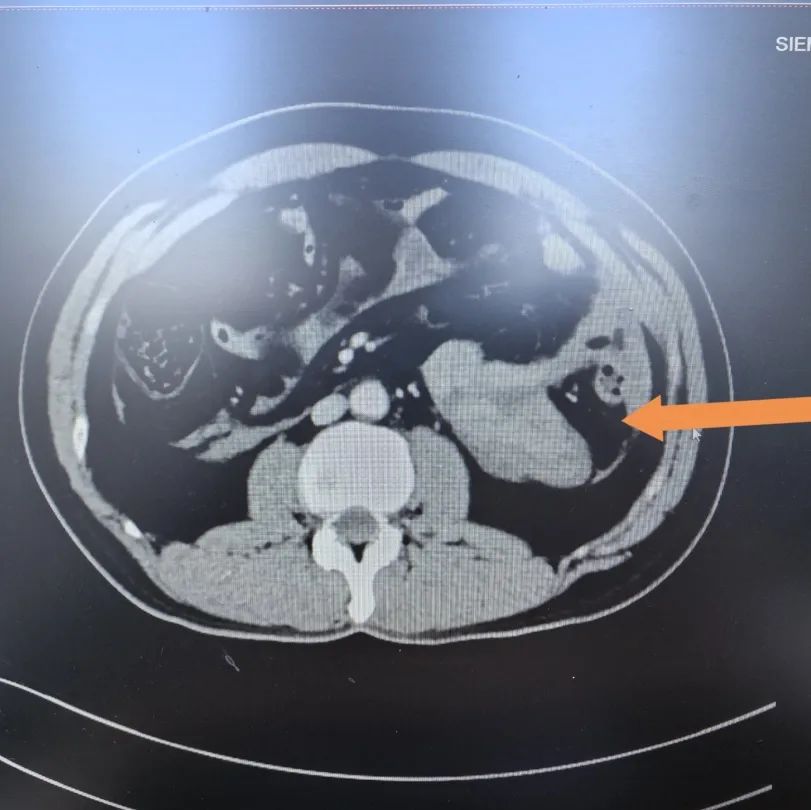

▲患者CT影像

遂即刻完善胸腹部增强CT,明确患者存在肠管损伤、肠系膜损伤出血,即刻转入手术室准备手术。